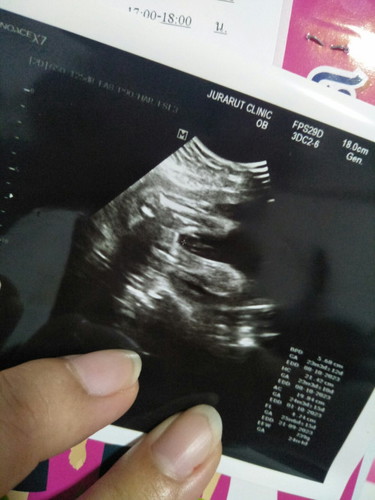

ภาพอัลตร้าซาวเพศหญิงมีสิทคลอดออกเปนชายไหม

แบบนี้น้องมีสิทธิ์เปนผู้ชายไหมค่ะ หมอบอกน้องเปนผู้หญิง😅

ของแม่หมอบอก80%ค่ะอีก20%รอดูตอนออกค่ะ

มีสิทธิ์นะคะ หญิงความชัวร์90% ชาย10%